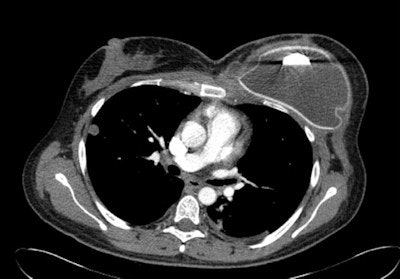

On CT, an intact silicone implant is characterized by an oval shape and homogeneous gray density within a surrounding high-density ring, he wrote. The implant often has contour deformities or implant bulges or hernias. The CT findings of intracapsular silicone implant rupture are similar to those of MRI, and the collapsed implant shell can usually be easily identified. Because silicone and soft tissues have similar radiodensities, extracapsular silicone can be difficult to identify on CT, but in most cases of extracapsular silicone implant ruptures, CT can detect the collapsed implant shell.

Because of CT's use of ionizing radiation and its low sensitivity and specificity, the modality should not be the study of choice, especially in young women, Juanpere stated. Most CT images of ruptured breast implants are incidental findings in asymptomatic patients or in already known failed implants.